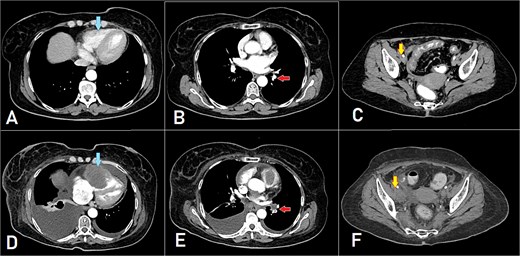

A computed tomography (CT) scan was performed, and the patient underwent a right hemicolectomy using a laparoscopic-assisted approach, with en bloc resection of the tumor and lymphadenectomy. The procedure was uneventful, with no intraoperative complications, and the patient had an unremarkable immediate postoperative recovery. The staging was determined as T4bN2bMx. Further imaging revealed enlarged mediastinal, supraclavicular, and retroperitoneal lymph nodes, with a solitary liver lesion (Fig. 1). A biopsy from the supraclavicular node indicated moderately differentiated adenocarcinoma of gastrointestinal origin. Molecular profiling showed wild-type RAS, intact MSI, mutant BRAF, and HER2 negative. The patient was started on capecitabine-oxaliplatin (CapeOX) with bevacizumab and completed 11 cycles with a marked clinical and radiological response (Fig. 2).

PET-CT scan at the corresponding cuts to Fig. 1 showing great metabolic and morphological regression regarding the previously seen (A) supraclavicular lymph nodes (arrow); (B) retroperitoneal lymph nodes (inferiorly pointing arrow) and hepatic lesion (superiorly pointing arrow); (C) mediastinal (para-oesophageal – station VIII) lymph node (arrow); and (D) retroperitoneal lymph nodes (arrow).